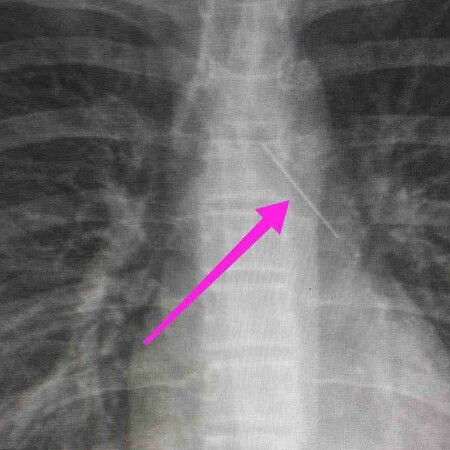

Ελλάδα Θεσσαλονίκη: Ανήλικη κατάπιε καρφίτσα, σωτήρια επέμβαση από τους γιατρούς Είχε σφηνωθεί στους βρόγχους THE LIFO TEAM

31.1.2022 Ελλάδα Θεσσαλονίκη: Ανήλικη κατάπιε καρφίτσα, σωτήρια επέμβαση από τους γιατρούς The LiFO team 31.1.2022 Είχε σφηνωθεί στους βρόγχους THE LIFO TEAM